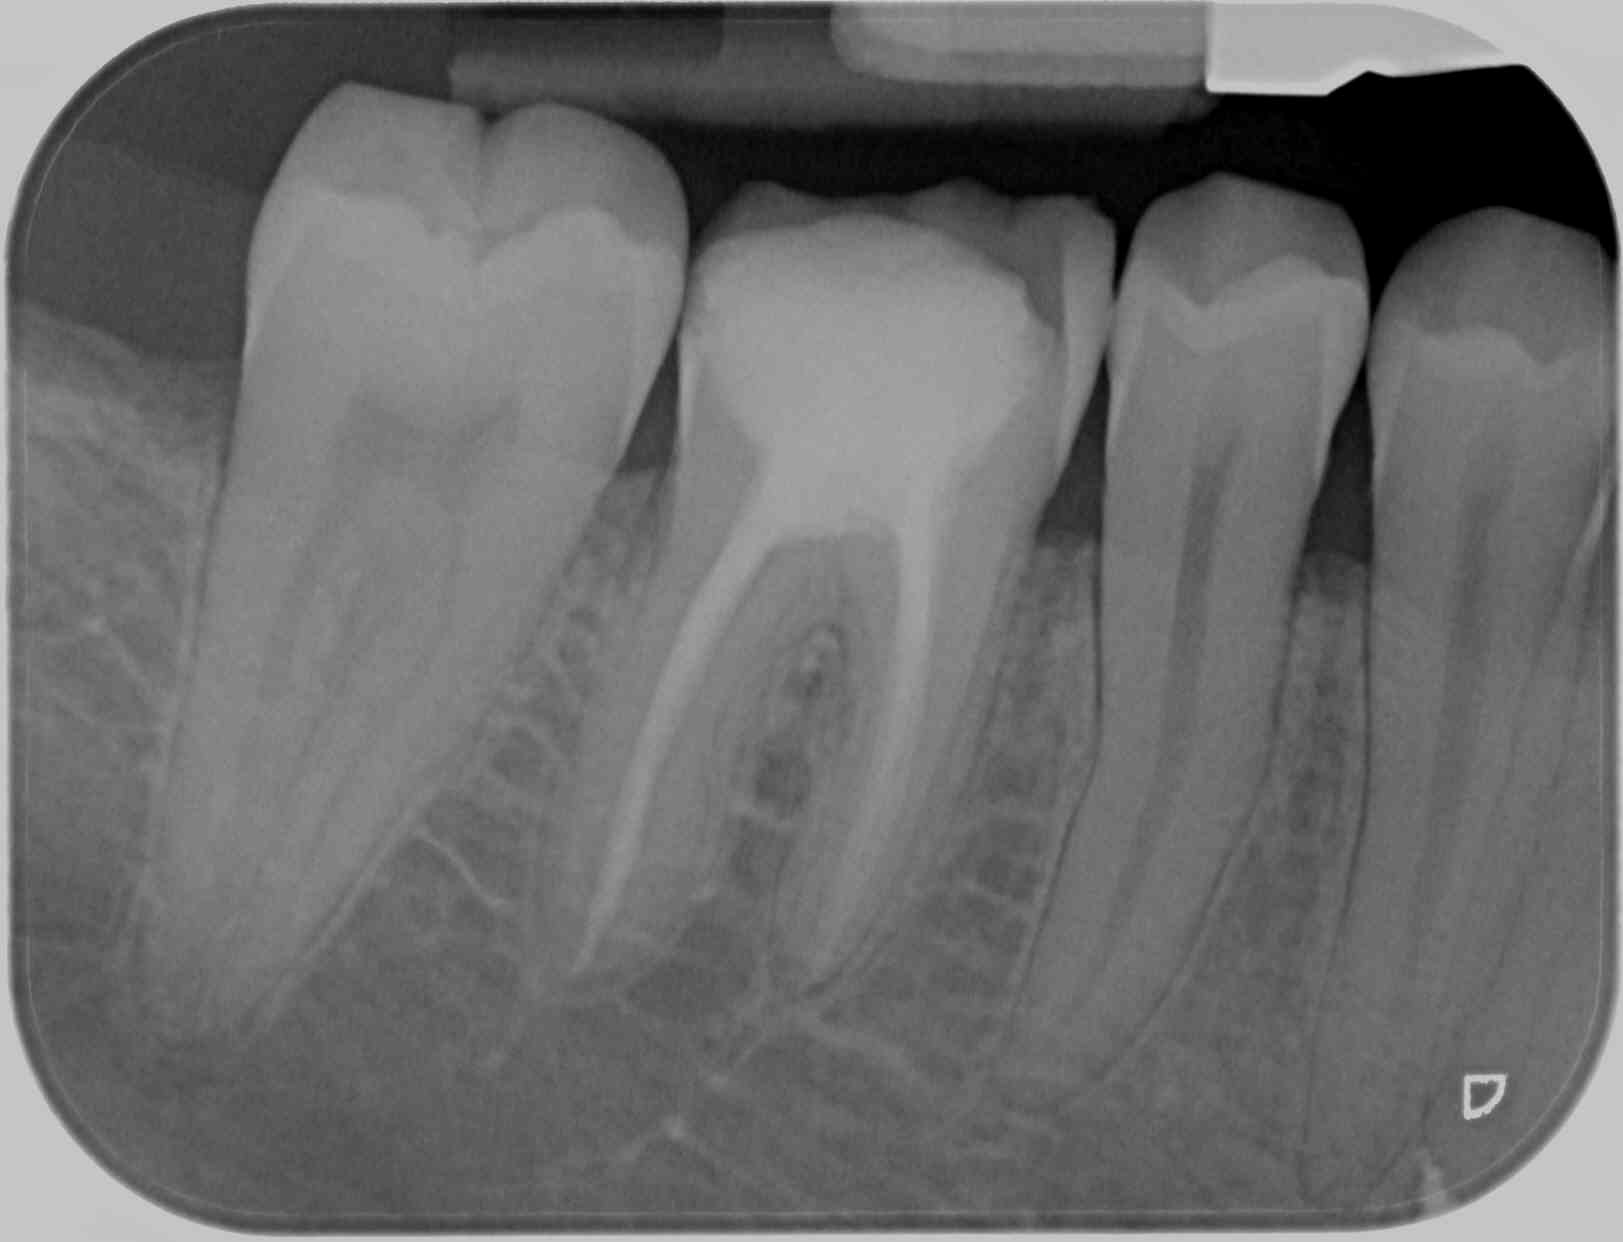

Patiente de 12 ans les 6 ont été extraites il y a 4 ans caries +++ et avis ortho

Partie dans la nature 3 ans revenue avec carie juxta gingivale sur 47 obligée de faire l endo mais aucune butée sur la racine D

J ai réussi l endo tant bien que mal en coupant mon cône de gutta

J’aimerai votre avis sur le pronostic du traitement endo et sur l’avenir de cette dent ?

Cette 7 a migré (ortho) en lieu et place de la 6. Elle devient par conséquent un élément primordial du calage occlusal chez cette gamine, il est indispensable de lui permettre de faire correctement son job si possible le plus longtemps possible. Elle est délabrée à raz de gencive voir plus bas: le collage va être acrobatique d’autant Plus que la valeur d’email résiduel semble faible, le plus étant l’enem du bien, il vaudrait mieux sceller, dans ce cas, donc couronne. Le panier CMU t’impose la CC, mais l’occlu Et le bon sens savent que ce matériau ne permet pas une intégration optimale. À toi de le faire comprendre à la maman: ici c’est CCM ou CCC scellée. Et si l’ortho a réussi la translation des 7, peut-être pourrait-il faire de même avec les 8.